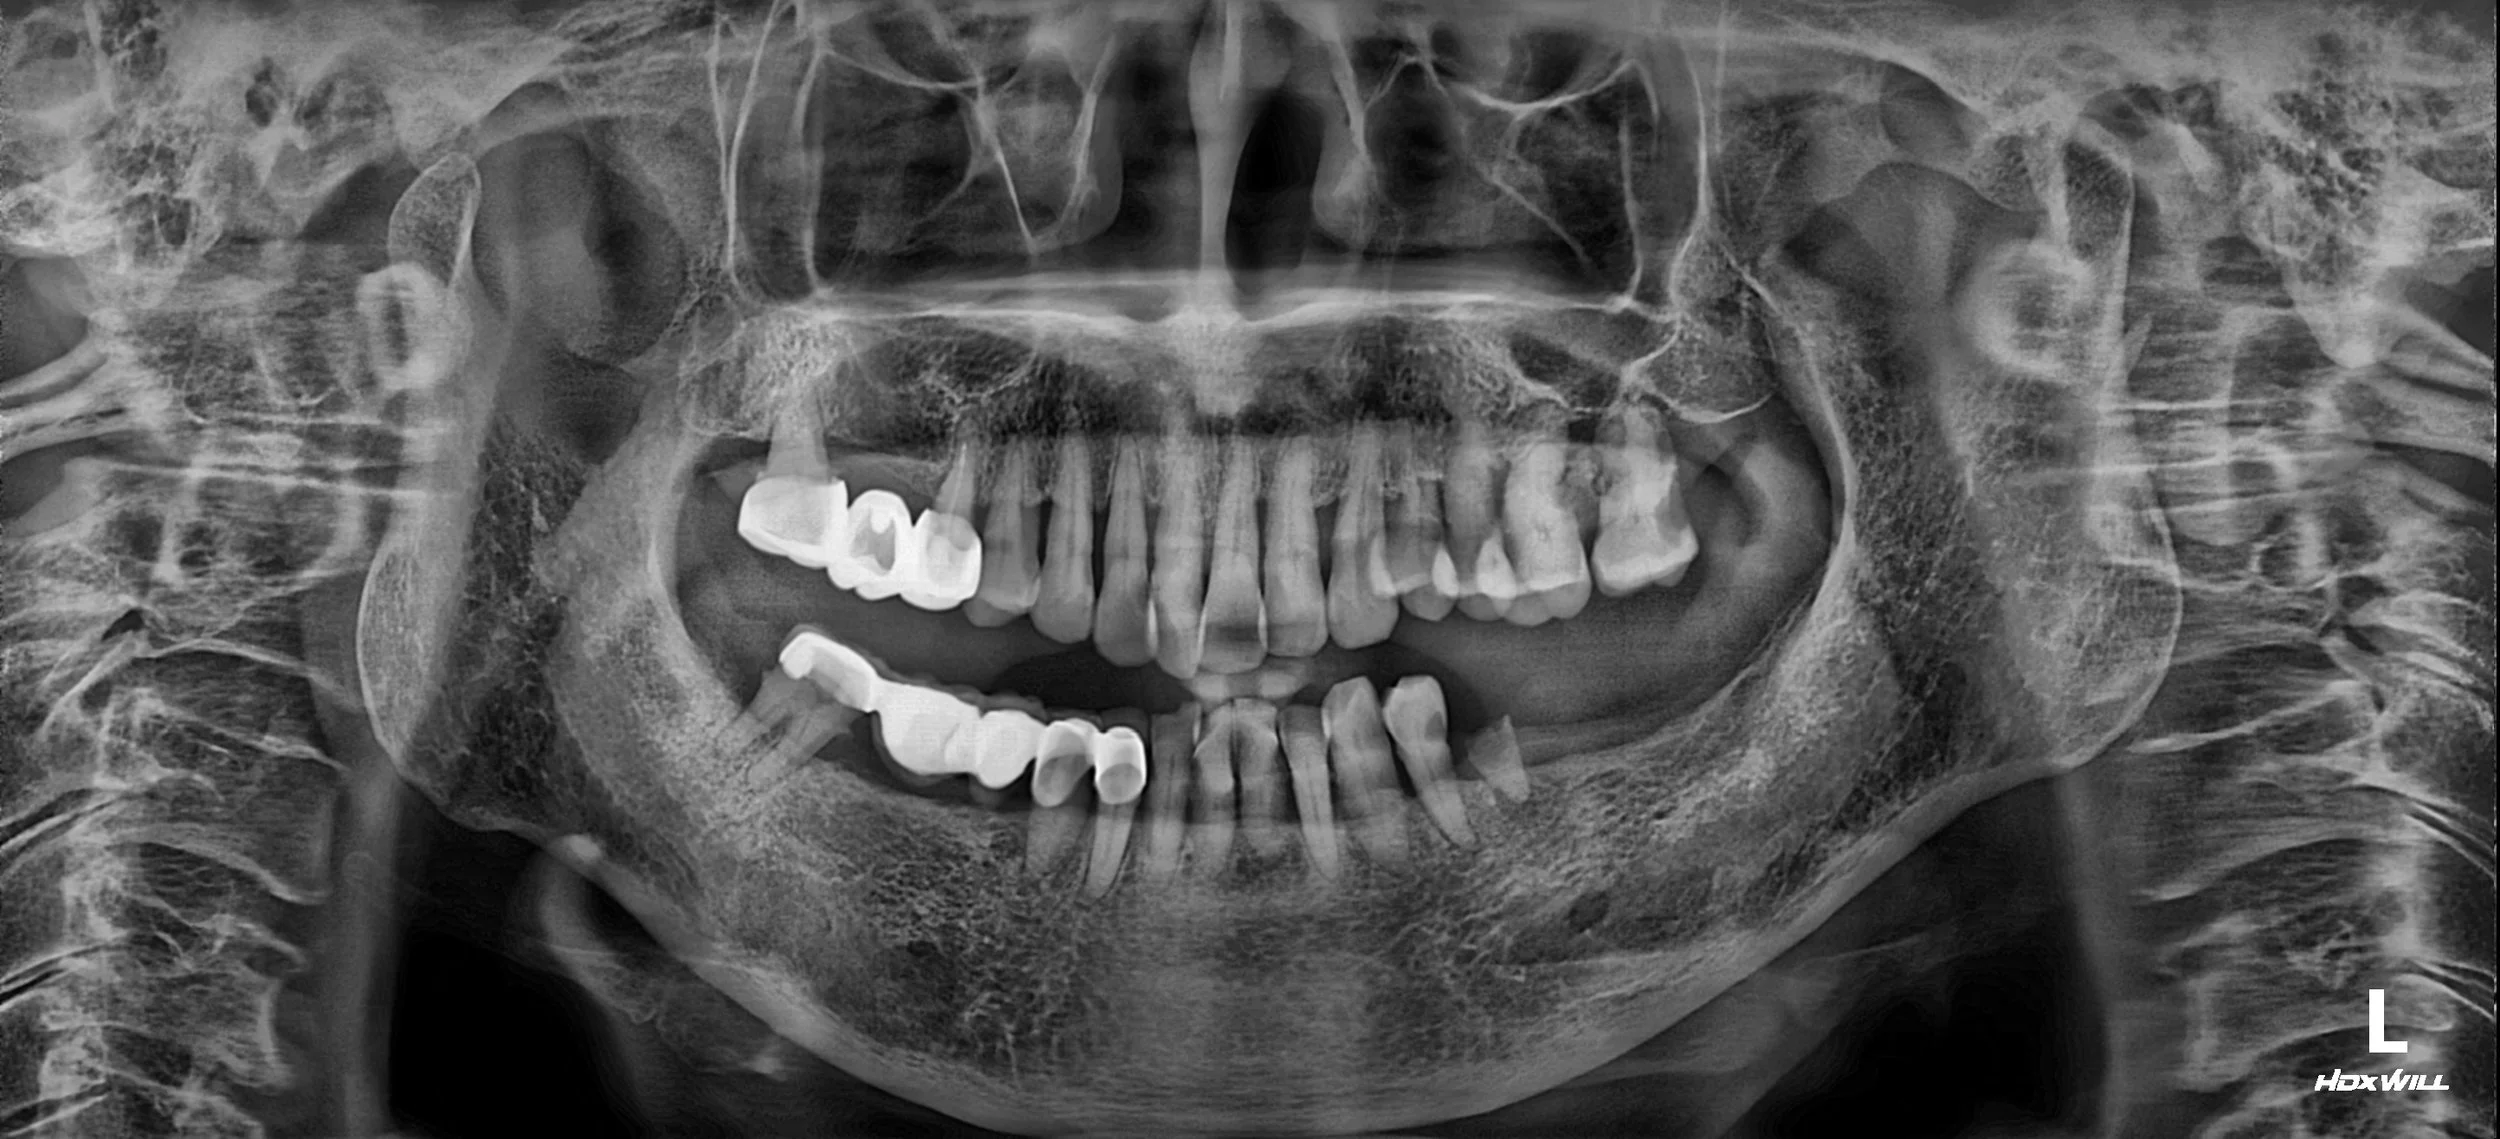

38. Comprehensive Full-Arch Reconstruction: Reversing the Domino Effect of Tooth Loss

Management of Generalized Severe Periodontitis and Posterior Bite Collapse in a Female Patient in her 60s. A Systematic Approach to VDO Recovery and Strategic Esthetic Rejuvenation.